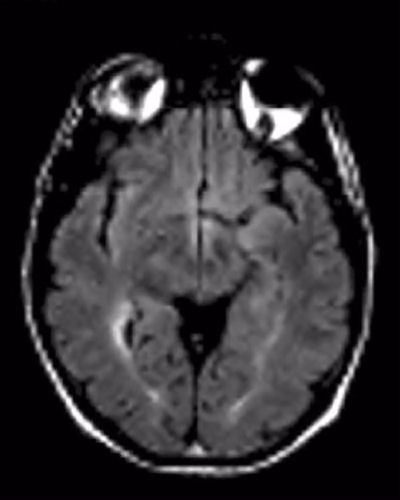

FLAIR MRI of the brain